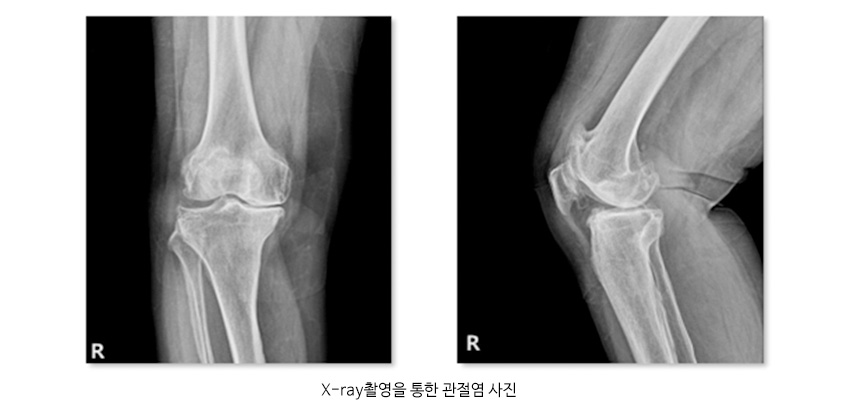

퇴행성 관절염을 진단하기 위해서는 X-ray촬영을 통하여 관절염 여부를 판정하며, 동반된 연부조직의 이상이나 관절연골의 상태를 보기 위해 MRI 촬영을 하기도하며 혈액검사와 관절액을 검사하여 다른 원인에 의한 관절염의 여부를 확인하기도 합니다.

관절염 사진 및 인공슬관절 치환술 사진